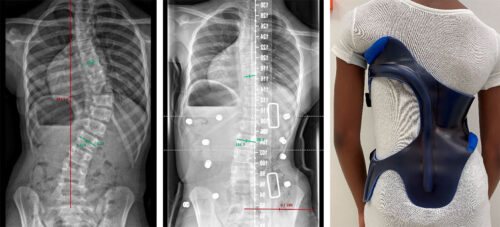

يُعدّ حزام اعوجاج العمود الفقري (الجنف) من أهم طرق العلاج غير الجراحية للمراهقين، خاصة في حالات الانحناءات التي تتراوح بين 20 و45 درجة. هذا الحزام يساعد على تصحيح و إبطاء تطور الانحناء حتى يكتمل نمو العظام. لكن يبقى السؤال الأكثر شيوعًا بين الأهل والمراهقين: متى يمكن التوقف عن ارتداء الحزام بأمان؟

التطور الكبير في تصميم الأحزمة الطبية جعل علاج اعوجاج العمود الفقري عند المراهقين أكثر نجاحًا وأقل إزعاجًا. باستخدام تقنيات التصوير الثلاثي الأبعاد والمحاكاة الرقمية، أصبح الحزام أكثر خفة وراحة، ويعطي نتائج أفضل في تصحيح الانحناء والتواء العمود الفقري.